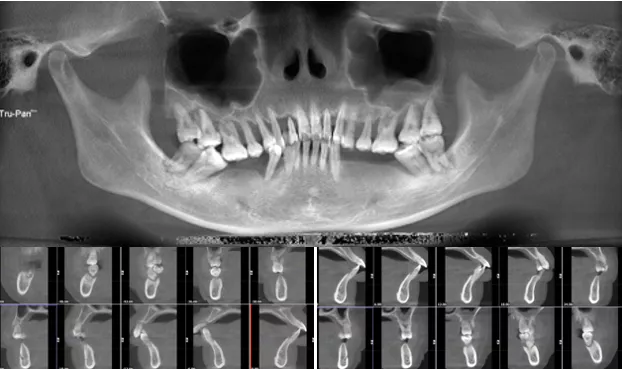

影像学检查

· 缺牙区骨量尚可,余留牙骨吸收至根尖1/3 。

· 双侧髁突骨皮质连续。

· 头影测量分析,临床诊断为:上颌前突,骨性二类错合畸形,上下中切牙及上下唇前突。

· 根据患者诉求、面型、剩余骨量、余留牙状况,拟拔除全部余留牙行全口种植固定修复。

· 上下颌计划各植入六颗straumann钛锆种植体行即刻种植即刻修复。

· 上下各计划植入6颗种植体。其中14、24种植体倾斜植入,15、25经牙槽嵴顶上颌窦提升植骨,其余牙位无需植骨。

种植体位置设计,可见上前牙唇侧骨量过丰满,需适量去骨。同时上下颌均需要截骨处理。